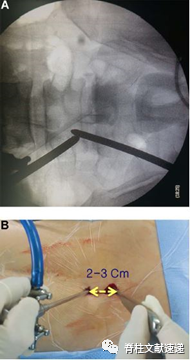

(二)定位与切口

UBE减压需要两个小切口,一个小切口约5-6mm,用于关节镜插入及持续生理盐水冲洗;另一个大切口约8-10mm,用作器械入口及生理盐水流出。使用扩张器逐层扩开椎旁肌肉,轻轻地将软组织推开创造空间。随着生理盐水的流入,空间形成并准备使用。

图注:术中腰椎透视图像关节镜通道与操作通道交汇。